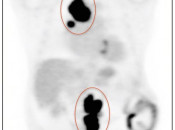

CT Portion of the Exam:  Its value lies in its excellent anatomic detail, as demonstrated in the case above.  In this patient presenting for post-treatment assessment of lymphoma, the CT clearly demonstrates abnormal soft tissue density above and below the diaphragm.  From the CT scan, we know abnormal soft tissue exists, its size and precisely where it is located. What we do not know from the CT scan is the answer to the ultimate clinical question: Does this remaining soft tissue represent active malignancy or post-therapeutic scarring — Does this patient still have cancer? For the answer, we must turn to the PET portion of the examination.

PET Portion of the Exam: Although of extremely limited anatomic value, the PET study has the impressive ability to determine whether the residual soft tissue on the CT scan represents active malignancy or post-therapeutic scar tissue. In this case, the intense metabolic activity is consistent with active lymphoma both above and below the diaphragm.